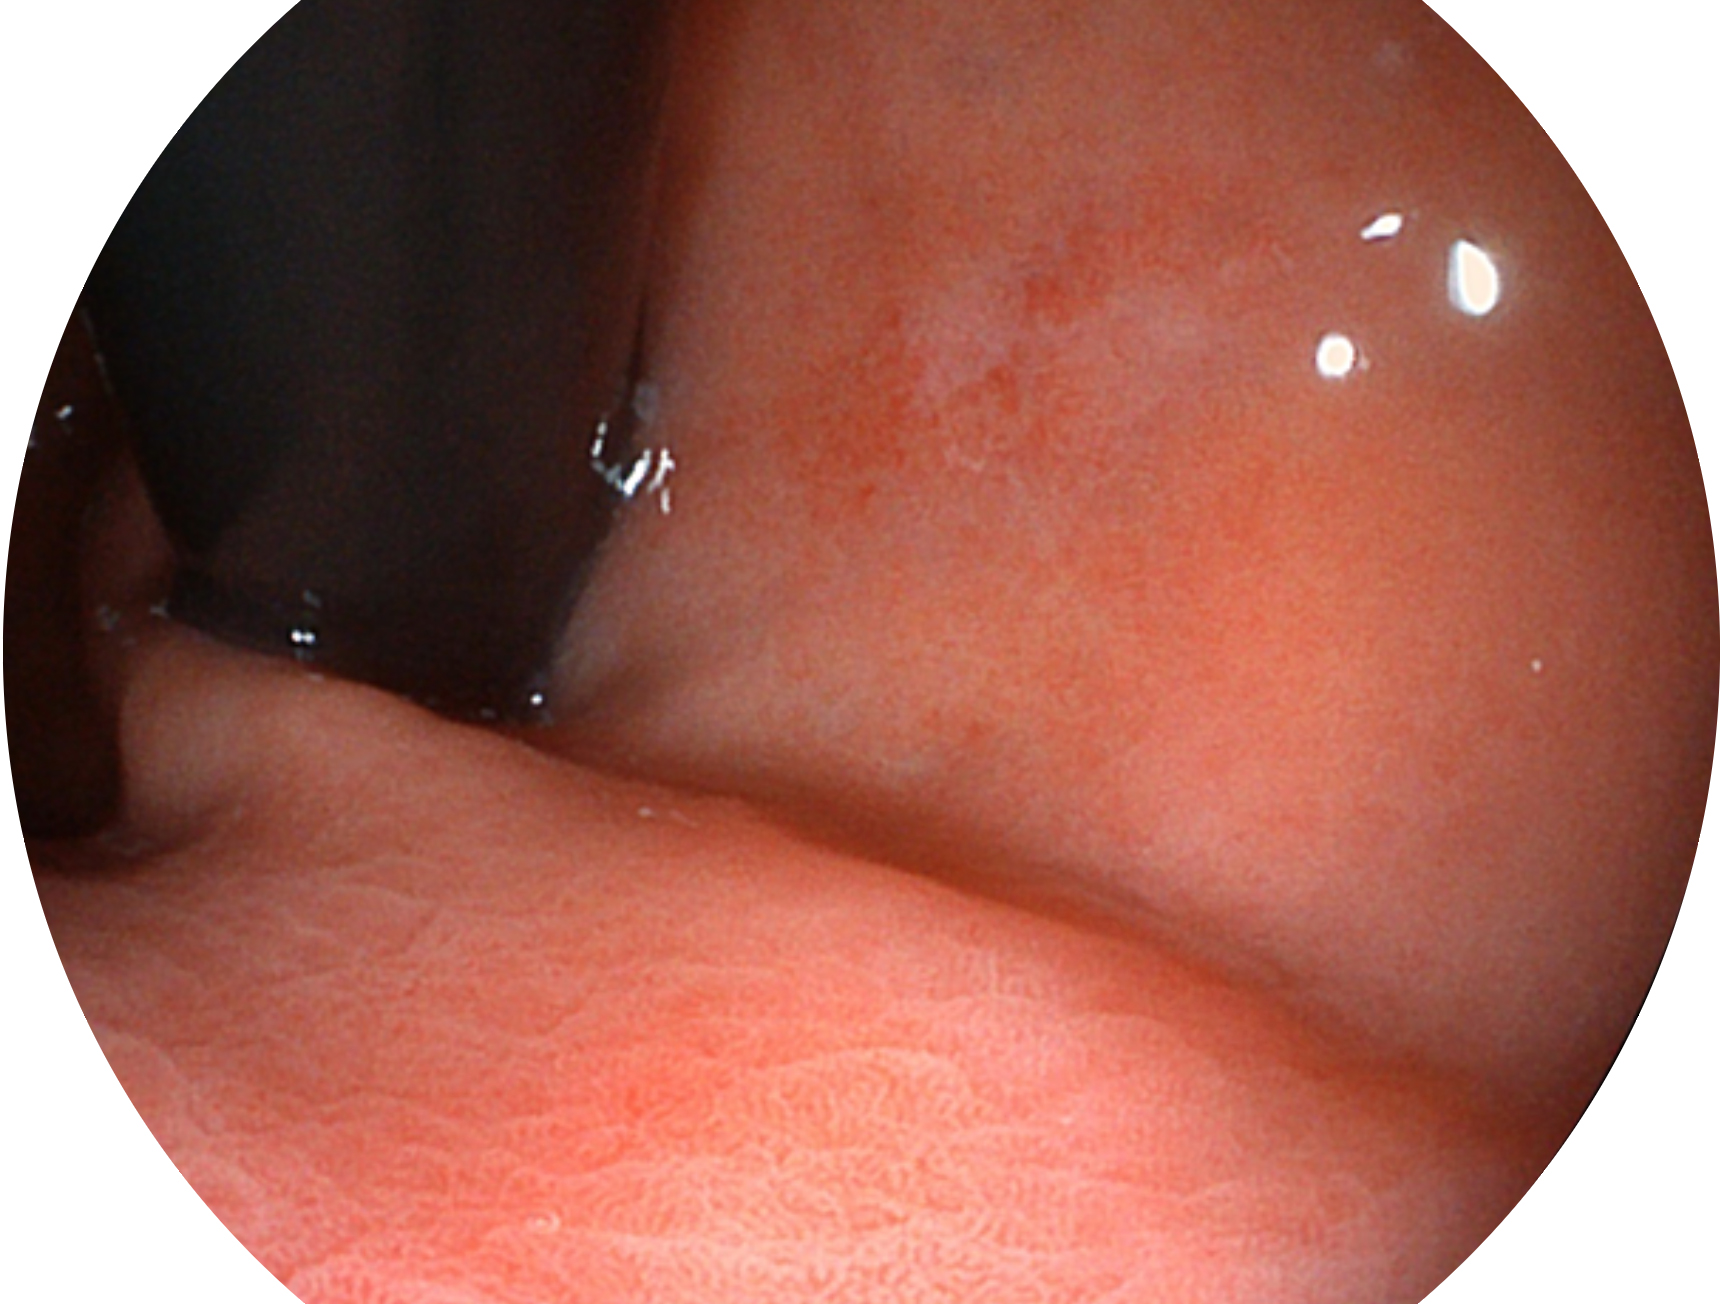

開立新開發(fā)的內(nèi)鏡染色技術(shù),主要是基于多波長(zhǎng)LED 光源的開發(fā),VLS-55Q 四波長(zhǎng)LED 光源是由四個(gè)不同顏色的LED光按照相應(yīng)照明模式所規(guī)定的特定發(fā)光比例進(jìn)行合束后形成,合束后形成的照明光的光譜由紅光、綠光、藍(lán)光及藍(lán)紫光這四個(gè)不同的波段范圍構(gòu)成。具有更高光譜自由度,通過(guò)光譜比例的控制,實(shí)現(xiàn)了聚譜成像技術(shù),英文全稱為“Spectral Focused Imaging, SFI”,縮寫為“SFI”和光電復(fù)合染色成像技術(shù),英文全稱為“Versatile Intelligent Staining Technology, VIST”,縮寫為“VIST”。